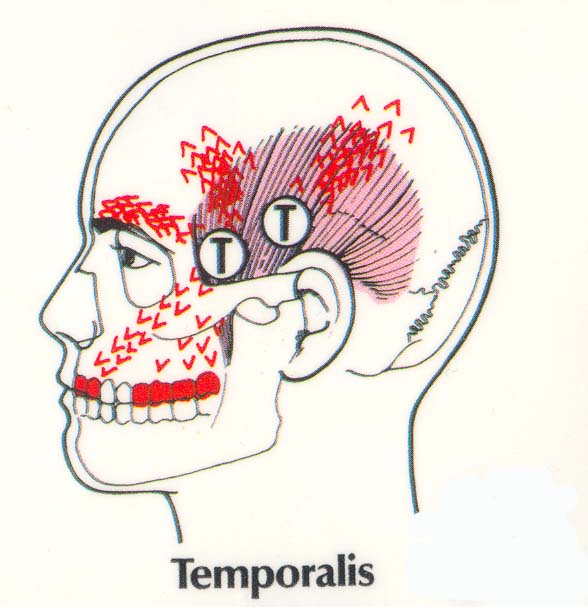

The pano verifies all the maxilla bone issues that include temporal bones at different heights, cloudy left sinus compared to right. Nasal septum is closing off the airway spaces. All the major dentistry is in the upper left. Many patients over the years that have a root canal in the middle of the skeletal asymmetry force like this example have a long history of migraine style headaches especially in the morning.

This patient has multiple issues. Her left neck is chronically tight, the left TMJ is painful, and she has regular left temporal headaches. The teeth were retrofitted between the bones in orthodontics and the continued growth of the mandible onl intensified the wedge. The force on this occlusion has been heavy posterior left all her life. The facial profile matches the shape of the force pattern. The history is mostly pain in the TM joints, pain in the teeth at times, but a lifetime history of left side sinus, temporal and neck pain.